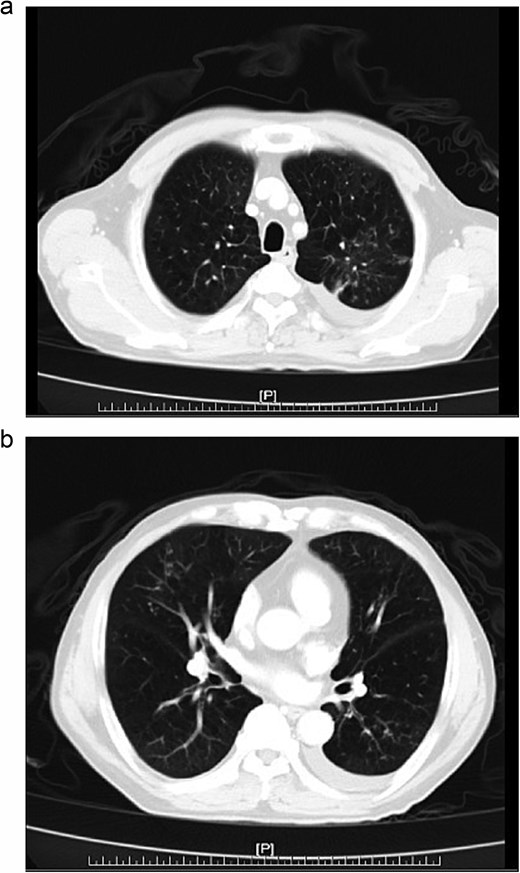

Further diagnostic evaluation with computed tomography (CT) of the abdomen and lungs was conducted. The abdominal CT revealed mild peritoneal thickening with multiple miliary nodules and omental cake with ascites (Fig. 1a and b), while the lung CT demonstrated multifocal of patches of centrilobular nodules and tree-in-bud in bilateral lungs (Fig. 2a, b).

(a, b) Abdominal CT, peritoneal thickening with multiple miliary nodules and omental cake with ascites.